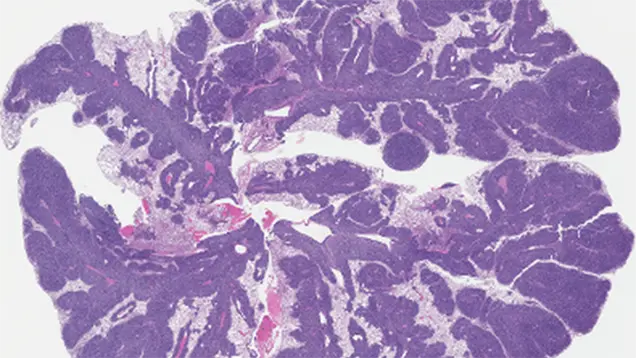

Cell State Plasticity in Rhabdomyosarcoma Progression

One of the main focuses of the Hebron lab is a pediatric soft tissue sarcoma called rhabdomyosarcoma (RMS), which resembles dedifferentiated skeletal muscle cells. As opposed to many adult cancers, pediatric cancers are more commonly associated with defects in developmental signaling programs than environmental exposures.

Because of altered developmental signaling, pediatric sarcoma cells often exhibit greater control over their differentiation than healthy cells, a phenomenon called cell-state plasticity. Cancer cells use this ability to evade therapies (resistance), spread to other areas of the body (metastasis), and regrow after treatment (relapse). We are working to understand the role of the proteins YAP1 and TAZ in rhabdomyosarcoma plasticity to identify new therapeutic strategies for patients with resistant, relapsed, or metastatic RMS.